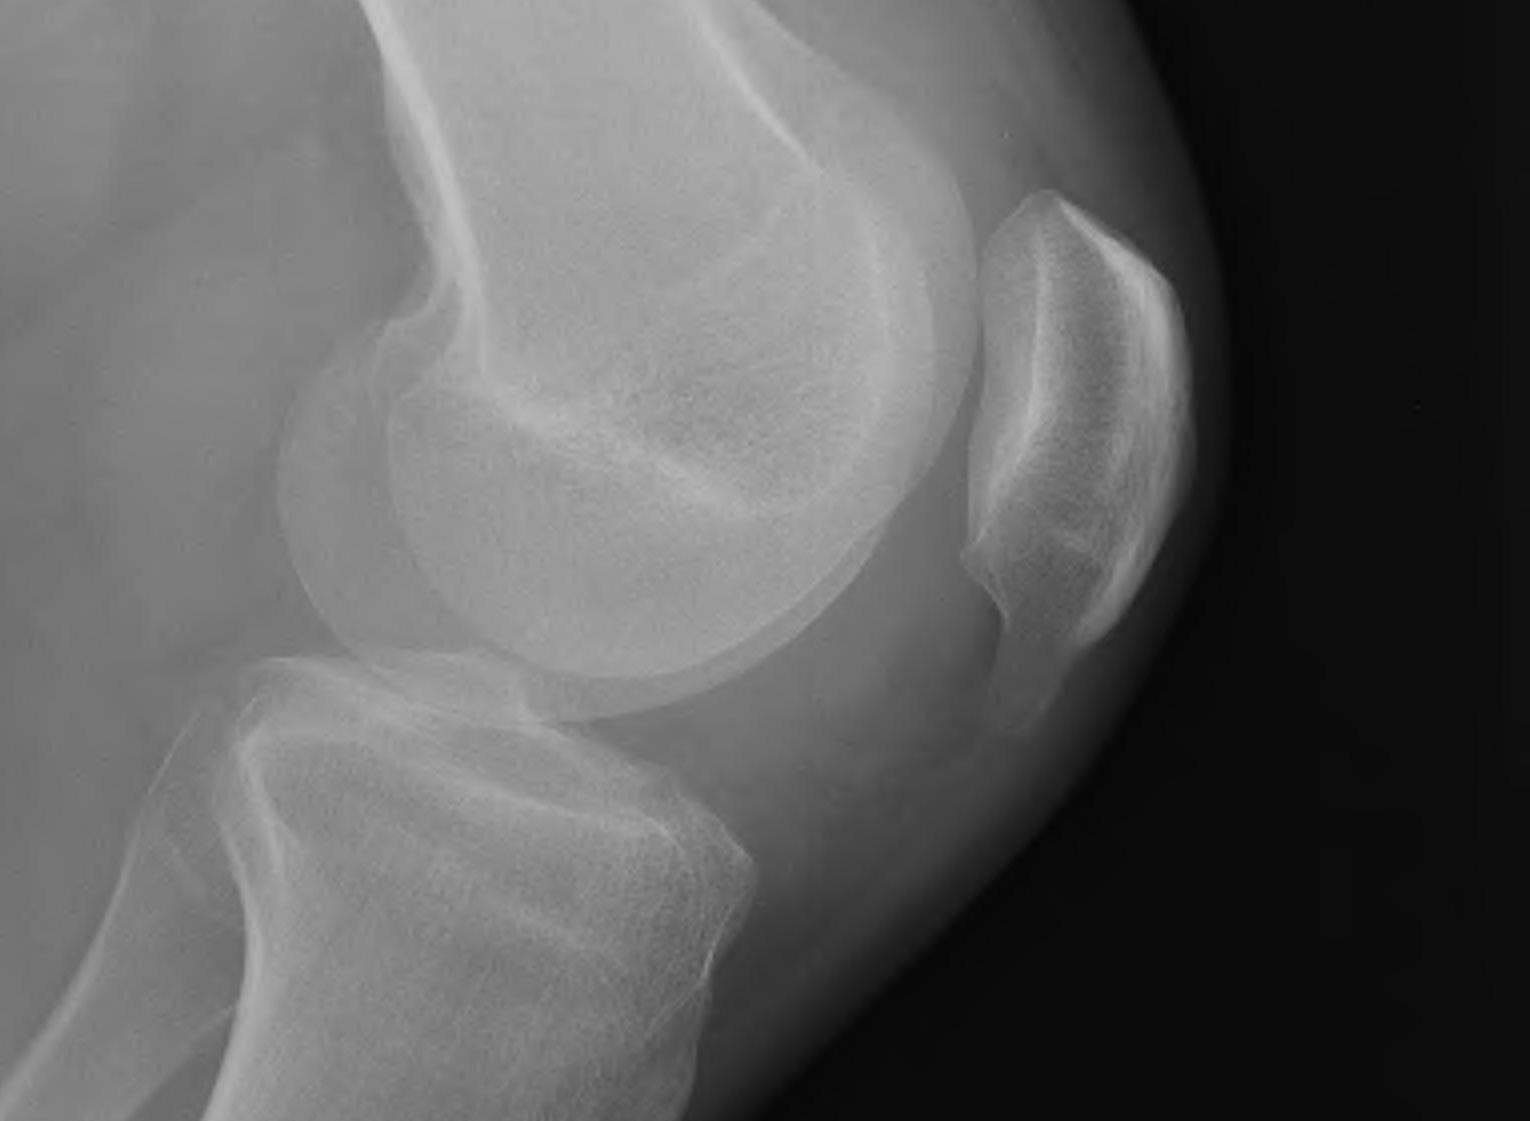

X-ray

Usually normal

May see

- traction spurs

- calcification of patella tendon